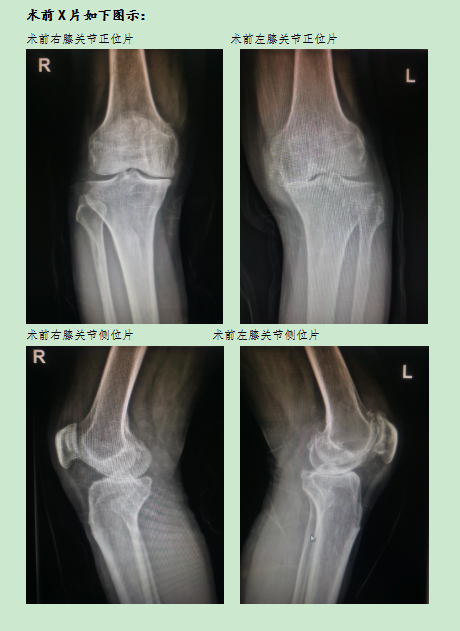

患者蔡某某,65歲,2014年出現(xiàn)雙側(cè)膝關(guān)節(jié)疼痛,至今雙側(cè)膝關(guān)節(jié)疼痛持續(xù)9年,嚴(yán)重影響正常生活。在長(zhǎng)時(shí)間行走、受涼后疼痛加重,偶伴輕度腫脹,因條件有限未予系統(tǒng)診療。近日雙側(cè)膝關(guān)節(jié)疼痛明顯加重尤以左側(cè)明顯,遂來(lái)我院骨科門(mén)診就診,以“雙側(cè)膝關(guān)節(jié)骨性關(guān)節(jié)炎”收住入院。

該患者入院后,完善相關(guān)檢查,蔡成成主任和主管醫(yī)生對(duì)患者全面評(píng)估后,制定出最佳的治療方案,鑒于患者右膝關(guān)節(jié)畸形尚不嚴(yán)重,活動(dòng)度尚可,計(jì)劃先行“左側(cè)全膝關(guān)節(jié)置換術(shù)”,待左膝關(guān)節(jié)傷口愈合、功能恢復(fù)后,再行“右側(cè)膝關(guān)節(jié)單髁置換術(shù)”,在醫(yī)護(hù)人員精心治療護(hù)理下,在患者及家屬配合下,順利為患者先后完成兩次手術(shù)治療。術(shù)后患者切口愈合良好,雙側(cè)膝關(guān)節(jié)屈伸活動(dòng)良好,兩次手術(shù)均在術(shù)后第二天下床活動(dòng),經(jīng)過(guò)為期三周的規(guī)范治療與功能鍛煉,該患者康復(fù)出院,出院時(shí)已擺脫輪椅自行下樓,完全恢復(fù)正常行動(dòng)。這是我科獨(dú)立成功完成的首例“人工膝關(guān)節(jié)單髁置換術(shù)”,標(biāo)志著我院骨科在關(guān)節(jié)置換領(lǐng)域向微創(chuàng)化、精準(zhǔn)化方向再次邁進(jìn)一步。